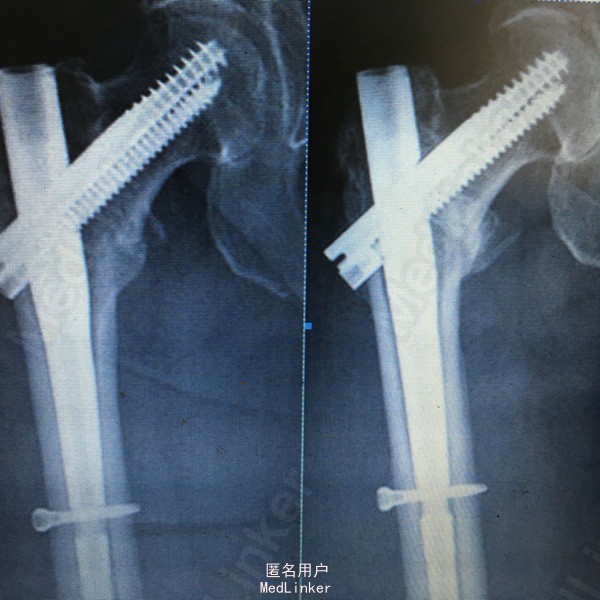

右侧股骨粗隆间骨折。 女患,79岁,a.术前X光片示股骨粗隆间骨折;b.术后X光片示骨折复位满意,内固定位置佳;c.术后12个月示骨折愈合良好

对移位的股骨粗隆间骨折采用手术治疗的方式已成为共识。PFNA、γ钉、PFNAII等器械对于粉碎性骨折却难以控制骨折端的加压滑动,过度的加压滑动将导致骨折端的塌陷、颈干角增加、股骨颈过度短缩、畸形愈合、下肢短缩、拉力螺钉脱出、内固定失效甚至治疗失败。 InterTan髓内钉是一种较新的内固定装置,为了克服以往髓内钉的缺点,其在股骨头颈内采用了双钉组合,插入主钉后,首先于股骨头颈内打入带防旋刀片的主拉力螺钉,再紧贴主拉力螺钉拧入小的加压螺钉,通过齿轮咬合原理,在轴向拧入小加压螺钉的同时,主拉力螺钉带动股骨头颈部后退从而实现了骨折端的加压。在本研究中,笔者认为InterTan的手术操作并不复杂,复位过程在骨折闭合状态下完成,本病例手术时间41min,时间较短从而降低了手术对患者的“二次打击”,利于术后康复。改良Harris髋部功能评分86,获得了满意的疗效。 另外,InterTan能够较好地实现骨折端的线性加压,锁定主拉力螺钉后可以防止股骨头颈的过度滑动,避免头颈塌陷,可以较好地传递人体体重力线。Megas等对股骨粗隆间骨折采用γ钉和PFNA作为内固定方式,其内固定失效的发生率分别为3.4%和4.6%,其他文献报道的应用髓内钉内固定股骨粗隆间骨折发生继发性股骨干骨折的发生率最高可达17%。在另外研究中,我们通过对100例平均(11.3±3.5)个月的随访未发现股骨颈塌陷、短缩、骨不连股骨干骨折后等并发症,进一步验证了InterTan作为一种髓内固定装置的生物力学优势。